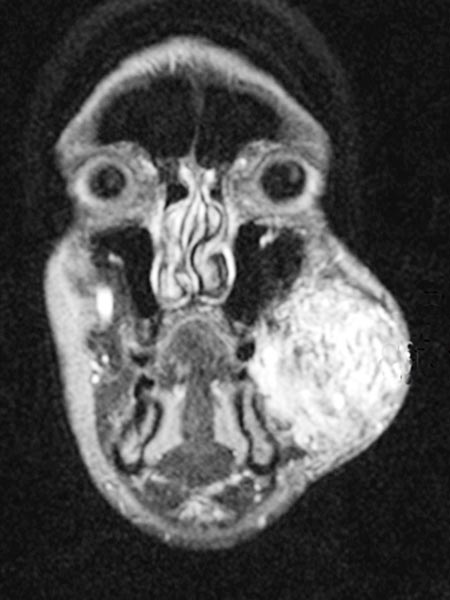

Axial, T2-weighted MRI at the level of the cheek shows the AVM to be relatively hyperintense with edema of the surrounding tissue and extension to the left mandible. In the rostral section some black flow voids are visible as a sign of arteries with fast flow within the AVM.

Inhomogeneous, peripheral enhancement of the proliferating AVM in this axial fat-suppressed T1-weighted MRI after contrast administration. No circumscribed component that is actually solid, unlike in a true vascular tumor.